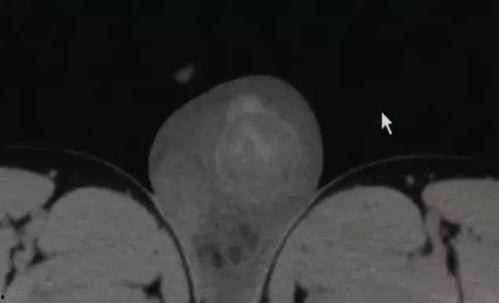

首先,让我们来揭开睾丸切除手术的神秘面纱。睾丸切除手术,顾名思义,就是将男性的睾丸从体内移除的手术。这个手术听起来可能有些恐怖,但其实它有着重要的医学意义。

睾丸是男性生殖系统中非常重要的器官,负责产生精子和男性激素。当睾丸出现问题,如睾丸癌、睾丸扭转等,医生可能会建议进行睾丸切除手术。